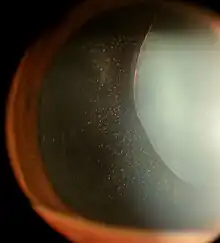

Ectopia Lentis in Marfan syndrome. Zonular fibers are being seen.

Ectopia lentis is a displacement or malposition of the eye's crystalline lens from its normal location. A partial dislocation of a lens is termed lens subluxation or subluxated lens; a complete dislocation of a lens is termed lens luxation or luxated lens.